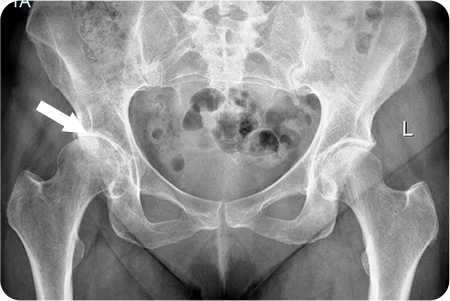

3

고관절 관절염

인공관절치환술

관절염으로 닳아버린 대퇴골두와 관골구를

정밀하게 절제합니다. 다리 길이와 관절 정렬을 맞추고,

움직임이 부드럽고 안정적인지 확인한 뒤 봉합

합니다.